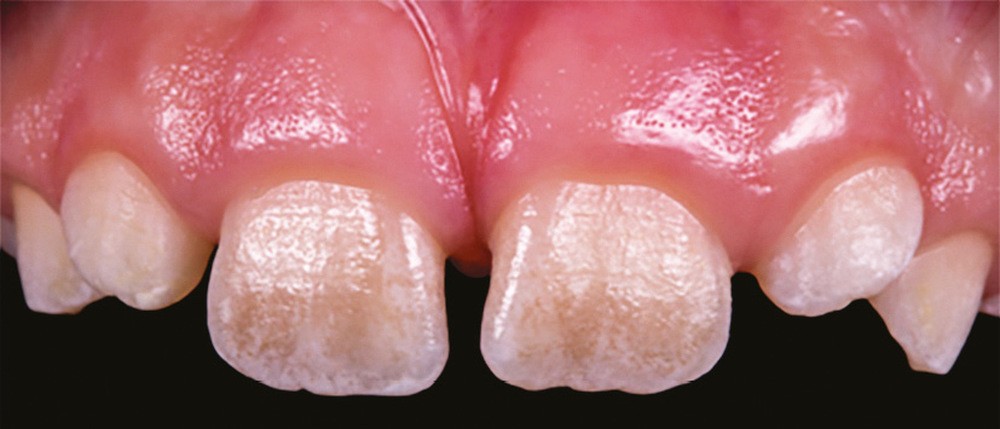

L’amélogenèse imparfaite est le nom donné à un groupe hétérogène de pathologies caractérisées par un défaut inné du développement de l’émail affectant toutes les dents des deux dentures. Ce sont des maladies génétiques dont l’origine est la mutation d’un gène impliqué dans l’amélogenèse. À ce jour, plus de 200 mutations différentes ont été identifiées, ce qui explique des phénotypes très variés [1]. Selon le stade de la maladie, l’émail est hypoplasique (défaut quantitatif), hypominéralisé, ou hypomature (défauts qualitatifs) : il est fin, fragile, tâché ou dyschromique. L’intensité des défauts peut être légère (forme frustre) ou très sévère, allant jusqu’à une absence totale d’émail. Son aspect est altéré par des dyschromies, fractures ou irrégularités de surface (fig. 1-4).